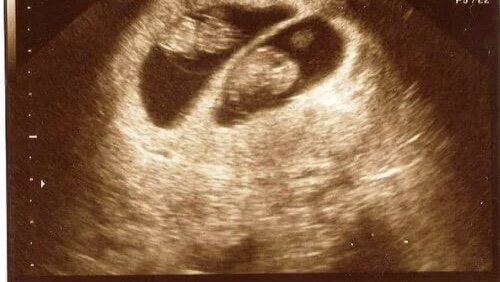

Приветствую Вас, дорогие читатели! Как Вы думаете, можно ли самому понять, что ты беременна не одним малышом? Без анализа на ХГЧ и узи! На ранних сроках, мне кажется, невозможно! Возможно, если ты сначала выносила и родила одного малыша - ты почувствуешь какие то отличия! Но если беременность первая, то... Лично я до узи и не подозревала о двойне! Хотя, когда моя гинеколог увидела анализ ХГЧ, то сразу предположила, т.к. он в разы больше. Но оказывается есть некоторые признаки, которые могут указывать...

Здравствуйте многоуважаемые читатели! Приветствую вас на канале «Записки многодетной мамы». Уверена, многие знают, что беременность приносит порой невероятные сюрпризы. Это и перепады настроения, и фантастические вкусовые причуды, а также неожиданное количество будущих детей. Вот о последнем я хотела бы поговорить и поделиться личным опытом. Как моя семья пережила новость что у нас будет двойня Итак, давайте знакомиться! Я многодетная мама. Моя вторая беременность была запланированная, а вот количество детей оказалось неожиданностью...